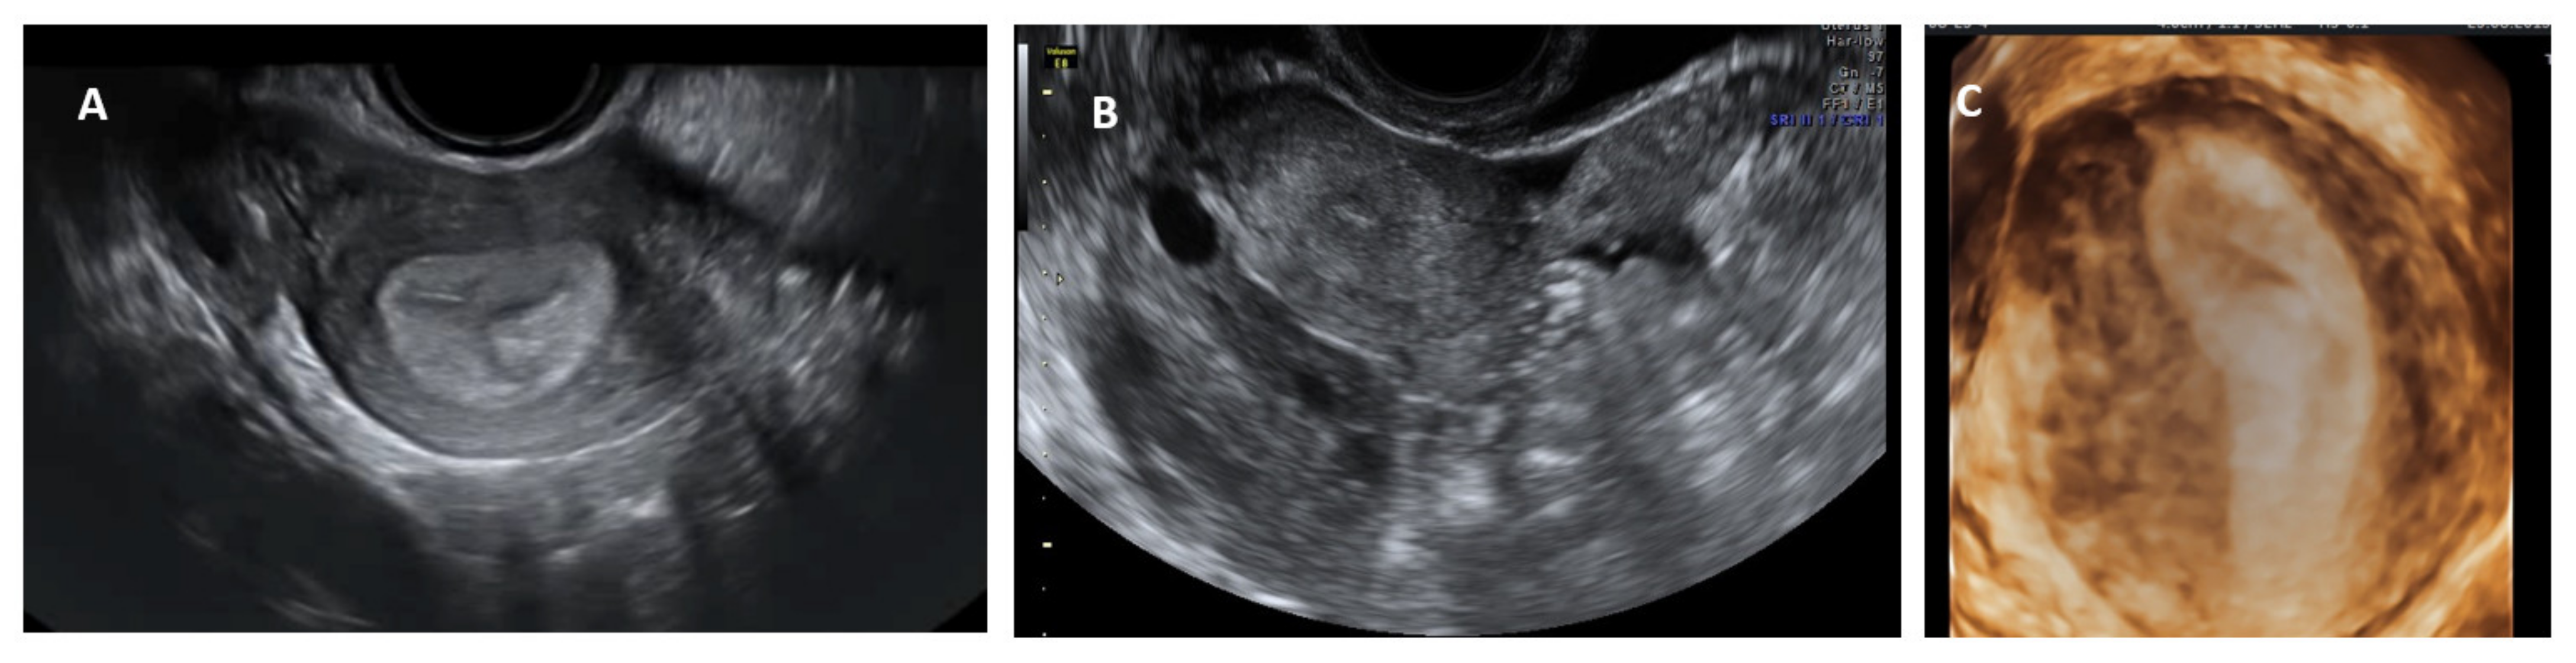

A unicornuate uterus may be difficult to diagnose on a conventional 2D scan. On a longitudinal scan, a normal looking sagittal axis of the uterus is seen on one side in the pelvis with no or a rudimentary uterine shadow on the other side. A rudimentary or severely hypoplastic uterine horn is seen as an isoechoic pear-shaped structure with or without a central thin echogenic endometrial line (Figure 5). On the transverse plane, the uterus is tapered to one side and at the level of the fundus, a beak like projection from the endometrial shadow (uterine angle or shoulder from where the interstitial portion of the fallopian tube starts) is seen only on one side (Figure 5). A 3D ultrasound, again, is confirmatory, demonstrating a banana shaped uterine cavity with a single interstitial portion of the fallopian tube seen in the coronal plane (Figure 3). Saline infusion sonography may be helpful in diagnosing communicating rudimentary horns as saline can be clearly seen in the unicornuate uterus, with passage into the rudimentary horn.

Figure 5. Unicornuate uterus: 2D transverse view showing only one uterine angle (shoulder)—Right (A); a small left rudimentary uterine horn (B) and banana-shaped uterine cavity on a 3D coronal plane (C).